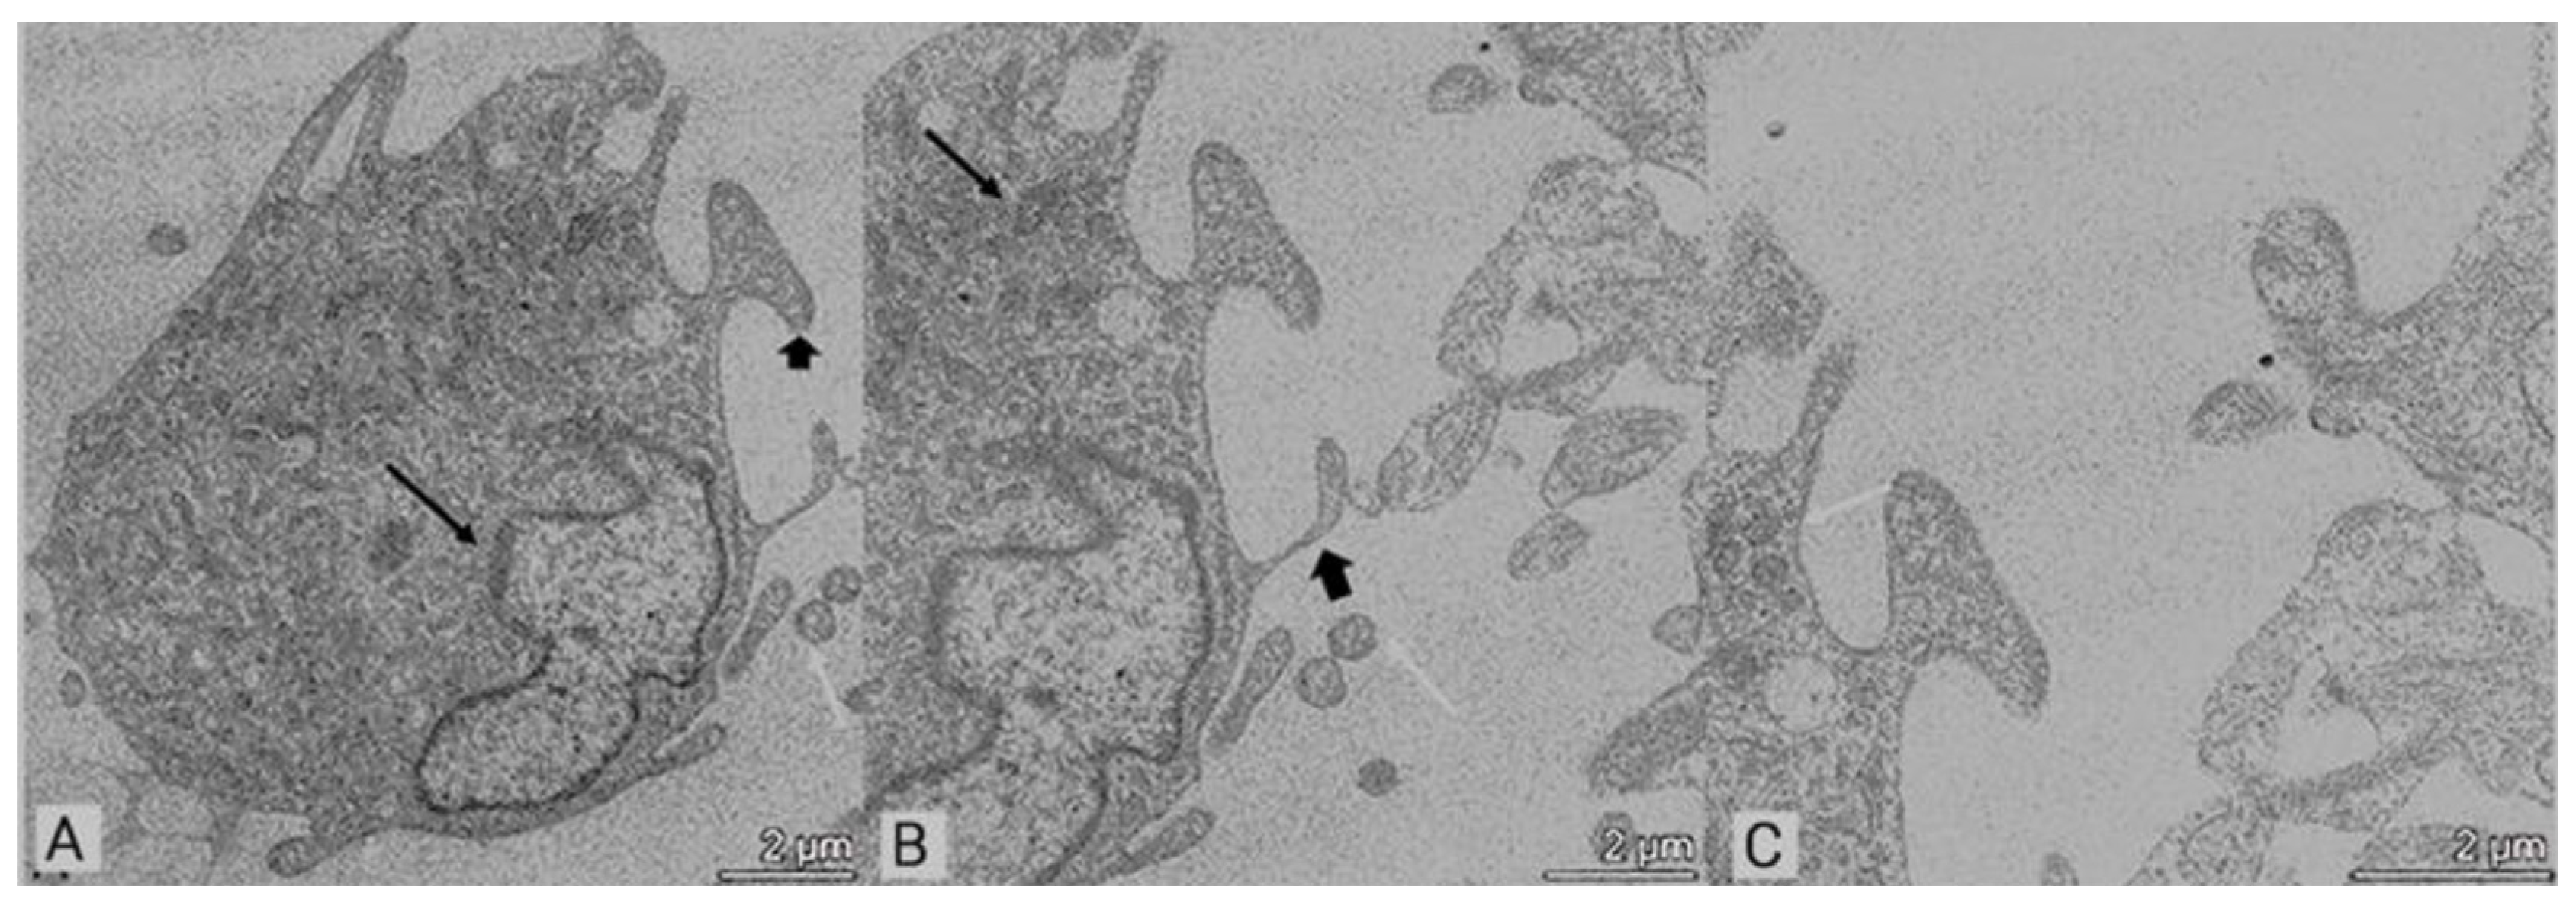

2.3. Transmission Electron Microscopy (TEM)

3.2. Transmission Electron Microscopy (TEM)